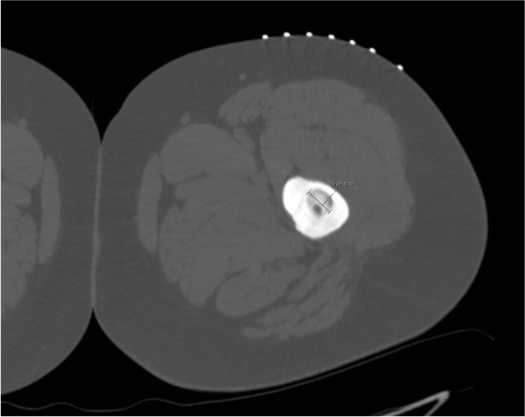

- CT (thin-slice, ≤1 mm): lucent nidus (<2 cm) surrounded by dense reactive cortical sclerosis — "halo sign"; central mineralized focus may be present

- "Halo sign": dense reactive sclerosis surrounding the central lucent nidus — the sclerosis is the conspicuous finding; the nidus is within it

- Nidus: rounded or ovoid lucency; may contain a dense central calcified focus (mineralized osteoid). Average diameter 5–15 mm

- Central mineralized focus within the lucency should not be confused with the reactive sclerosis — the probe tip targets the lucent nidus around it